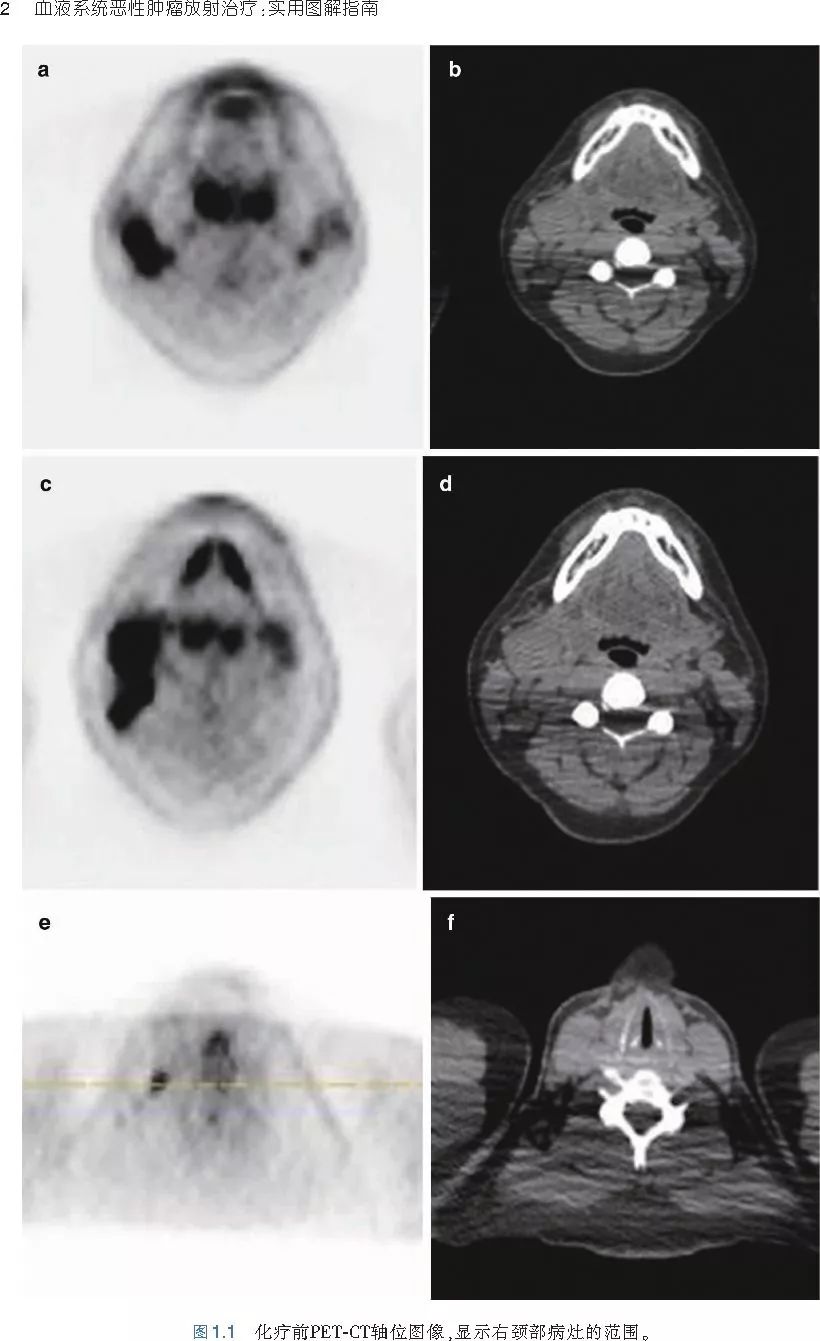

❤ 涵盖霍奇金淋巴瘤、非霍奇金淋巴瘤和白血病等患者的具体病例。

❤ 展开疾病诊断、病理描述及治疗方向的详细阐述,包含医学影像,图文并茂,深入浅出。

❤ 对当今血液恶性肿瘤放疗的价值、具体的实施方式、剂量和时机等,做了很详细的经验总结并提出了未来的研究方向。

❤ 对放射肿瘤学医师的临床决策提供宝贵的帮助,对血液病医师的临床诊疗也有指导意义。